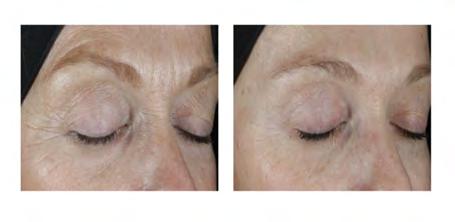

Aging skin is a topic most of us have been thinking about for years. The internet is full of promises for youthful-looking skin, but it can be overwhelming to separate fact from fiction. As someone who owns a MedSpa and works with clients every day, I’ve seen firsthand what works and what doesn’t. Let’s explore some triedand-true methods for maintaining healthy, glowing skin over 40.

Recently, a long-time client, Mary, came in for a skin consultation. She shared her frustration about trying every anti-aging cream out there with little to no results. She was ready for a change but didn’t want to go under the knife. I assured her that while creams can help with hydration and surface-level fine lines, they aren’t magic potions for deeper wrinkles or sagging skin. We discussed non-invasive treatments like microneedling and ultherapy, which stimulate collagen and elastin production to firm the skin. Mary decided to start with a series of

microneedling. Proud to say she comes in glowing now, thrilled with the subtle but noticeable improvements in her skin’s texture.

Then there’s Melissa, who was so skeptical about fillers and Botox. “Aren’t they just for people who want to look plastic?” she asked. This is a common misconception. When done correctly, injectables enhance your natural beauty without making you look ‘overdone.’ Melissa decided to try a little filler to smooth out her smile lines and Botox to smooth her crows feet. She was amazed at how refreshed she looked — like a more rested version of herself. Her friends noticed too, commenting that she looked vibrant and full of energy.

The key takeaway? It’s not about turning back the clock but about embracing your skin’s journey. Professional treatments like microneedling, Ultherapy, and injectables are tools to enhance what you already have. If you’re ready to explore options that actually work for mature skin, I’d love to help guide you on this journey.

After all, you deserve to feel beautiful at every age!